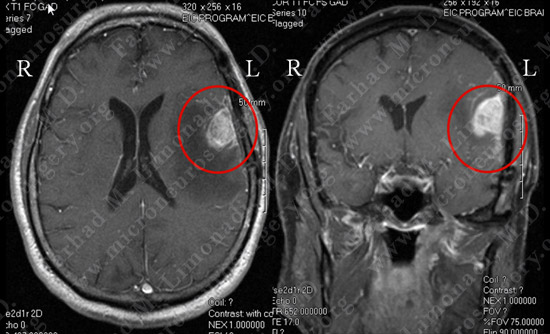

Imaging

MRI scan of the patient’s brain shows a large dural based tumor in the left frontoparietal convexity overlying the speech cortex, with significant vasogenic edema.